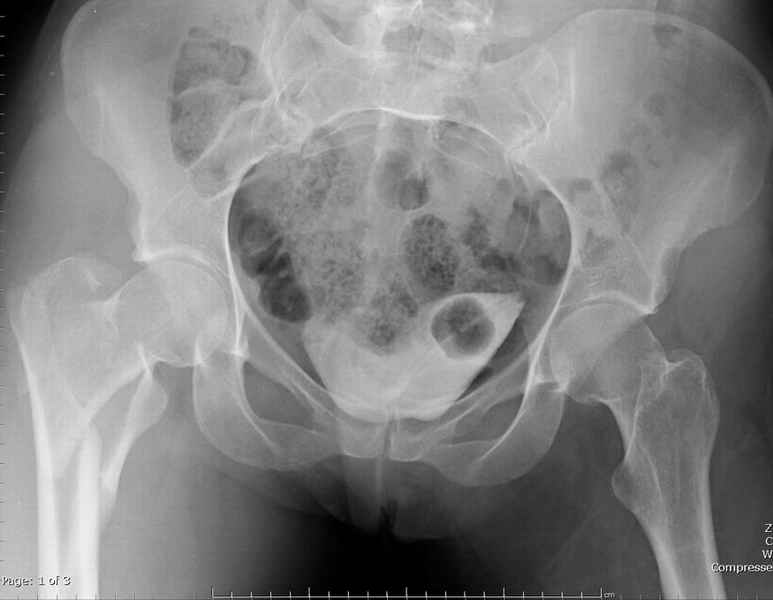

Ap pelvis Rt sub-intra trochanteric Fracture, AP Rt hip, Postop Blade Fixation